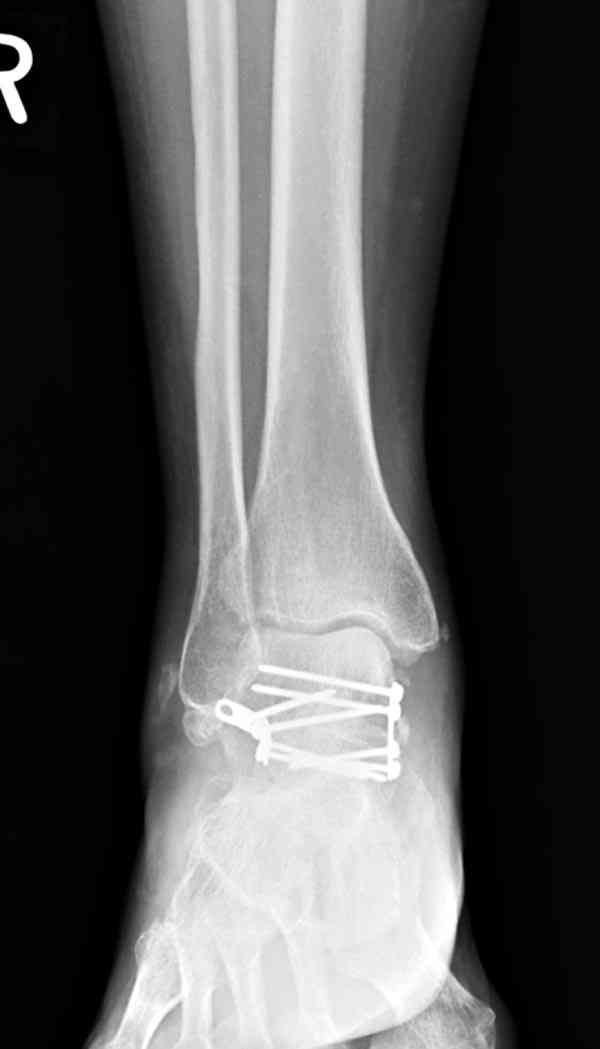

Случай с множественным оскольчатым переломом тарана оперированный из двойного доступа.

Через 8 мес.: